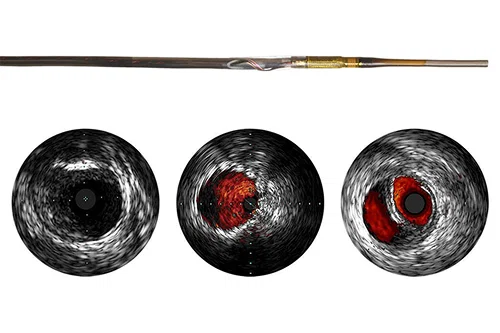

Refinity Short-tip rotational IVUS catheter

Philips’ next generation rotational IVUS catheter. With exceptional deliverability, it navigates through challenging lesions with ease. With 5F guide compatibility, it enables radial access and with 45 MHz high resolution image, it creates clear, crisp images for accurate vessel interpretation and lesion assessment.